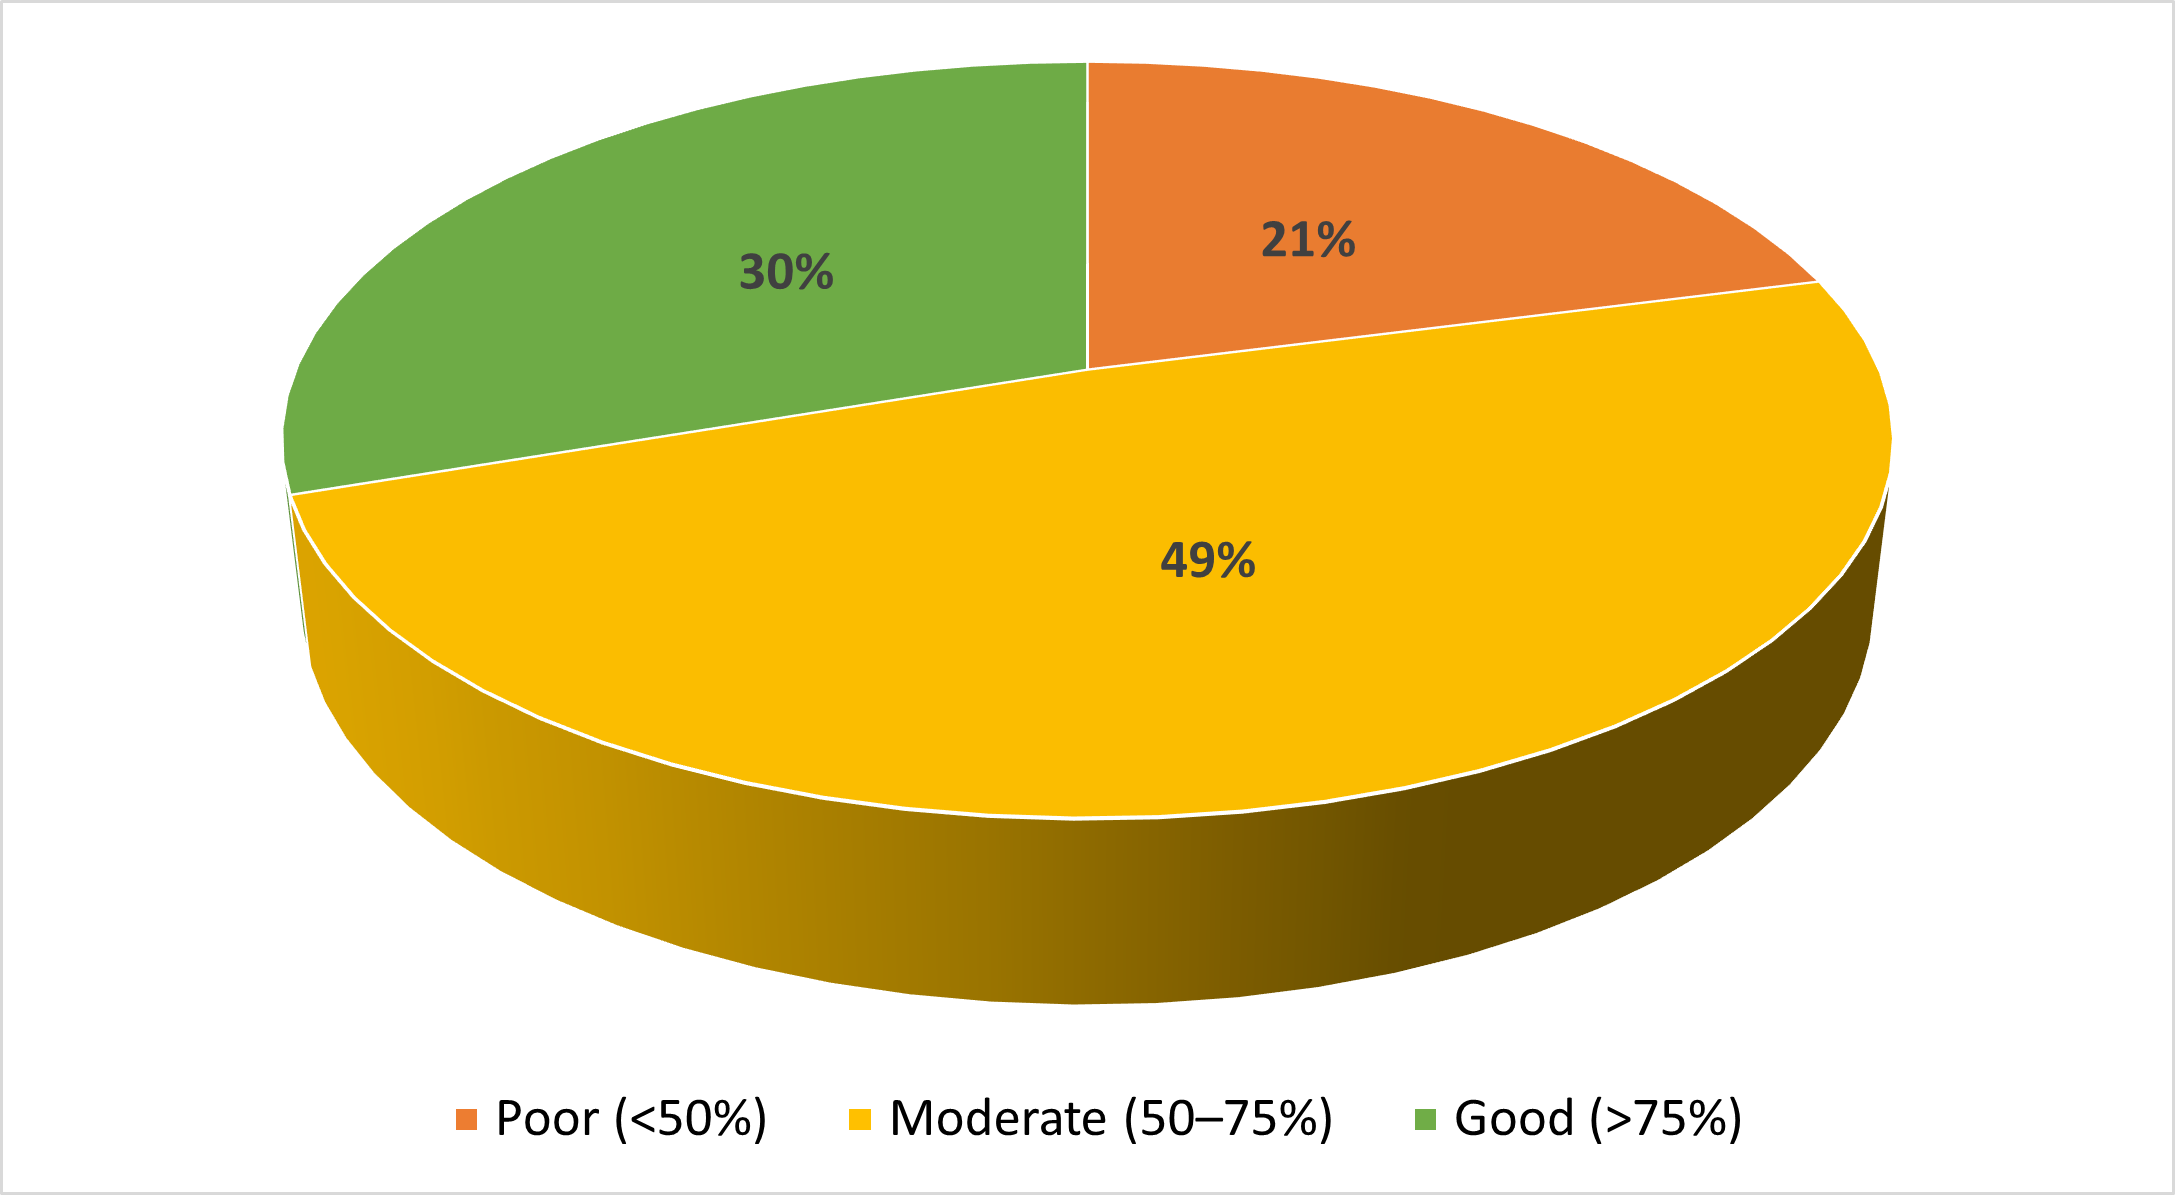

Quality Improvement Projects | Dec 01, 2025

Implementing a Prediabetes Screening Algorithm to Improve Identification and Referrals in Primary Care

Almost half (49%) of the United States population has prediabetes or type 2 diabetes. Type 2 diabetes is associated with...Read More